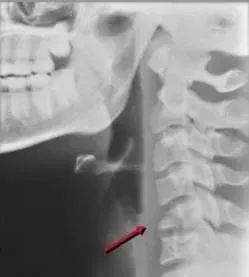

五、齿突骨折

多由过伸性损伤造成,常伴有C1向前滑脱,属于稳定性骨折。

另一患者